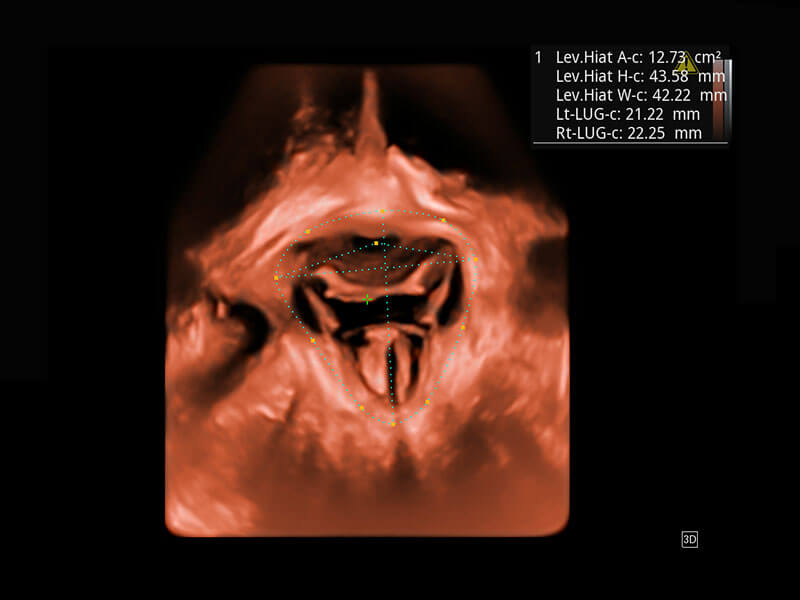

P60为盆底超声检查提供应用方案,多种腔内及腹部容积探头提供从二维、三维到四维的优异图像品质,实时快速三维容积数据获取,专业的测量工具包等人性化设计,为超声医生诊断提供有力保障。

Lev.Hiat A-r: 16.33 cm2

Lev.Hiat H-r: 53.70 mm

Lev.Hiat W-r: 43.96 mm

Lt-LUG-r: 24.16 mm

Rt-LUG-r: 19.94 mm

能够简化盆底检查的操作流程,可在二维模式及三维成像模式下实现一键自动提取出标准切面、自动识别当前切面、自动测量,提升盆底检查的高效性,同时也能让青年医生快捷的获得准确的检查结果。